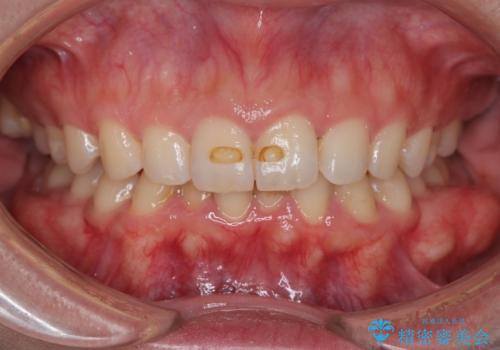

【インビザラインとワイヤー矯正】がたつきと噛み合わせを改善!